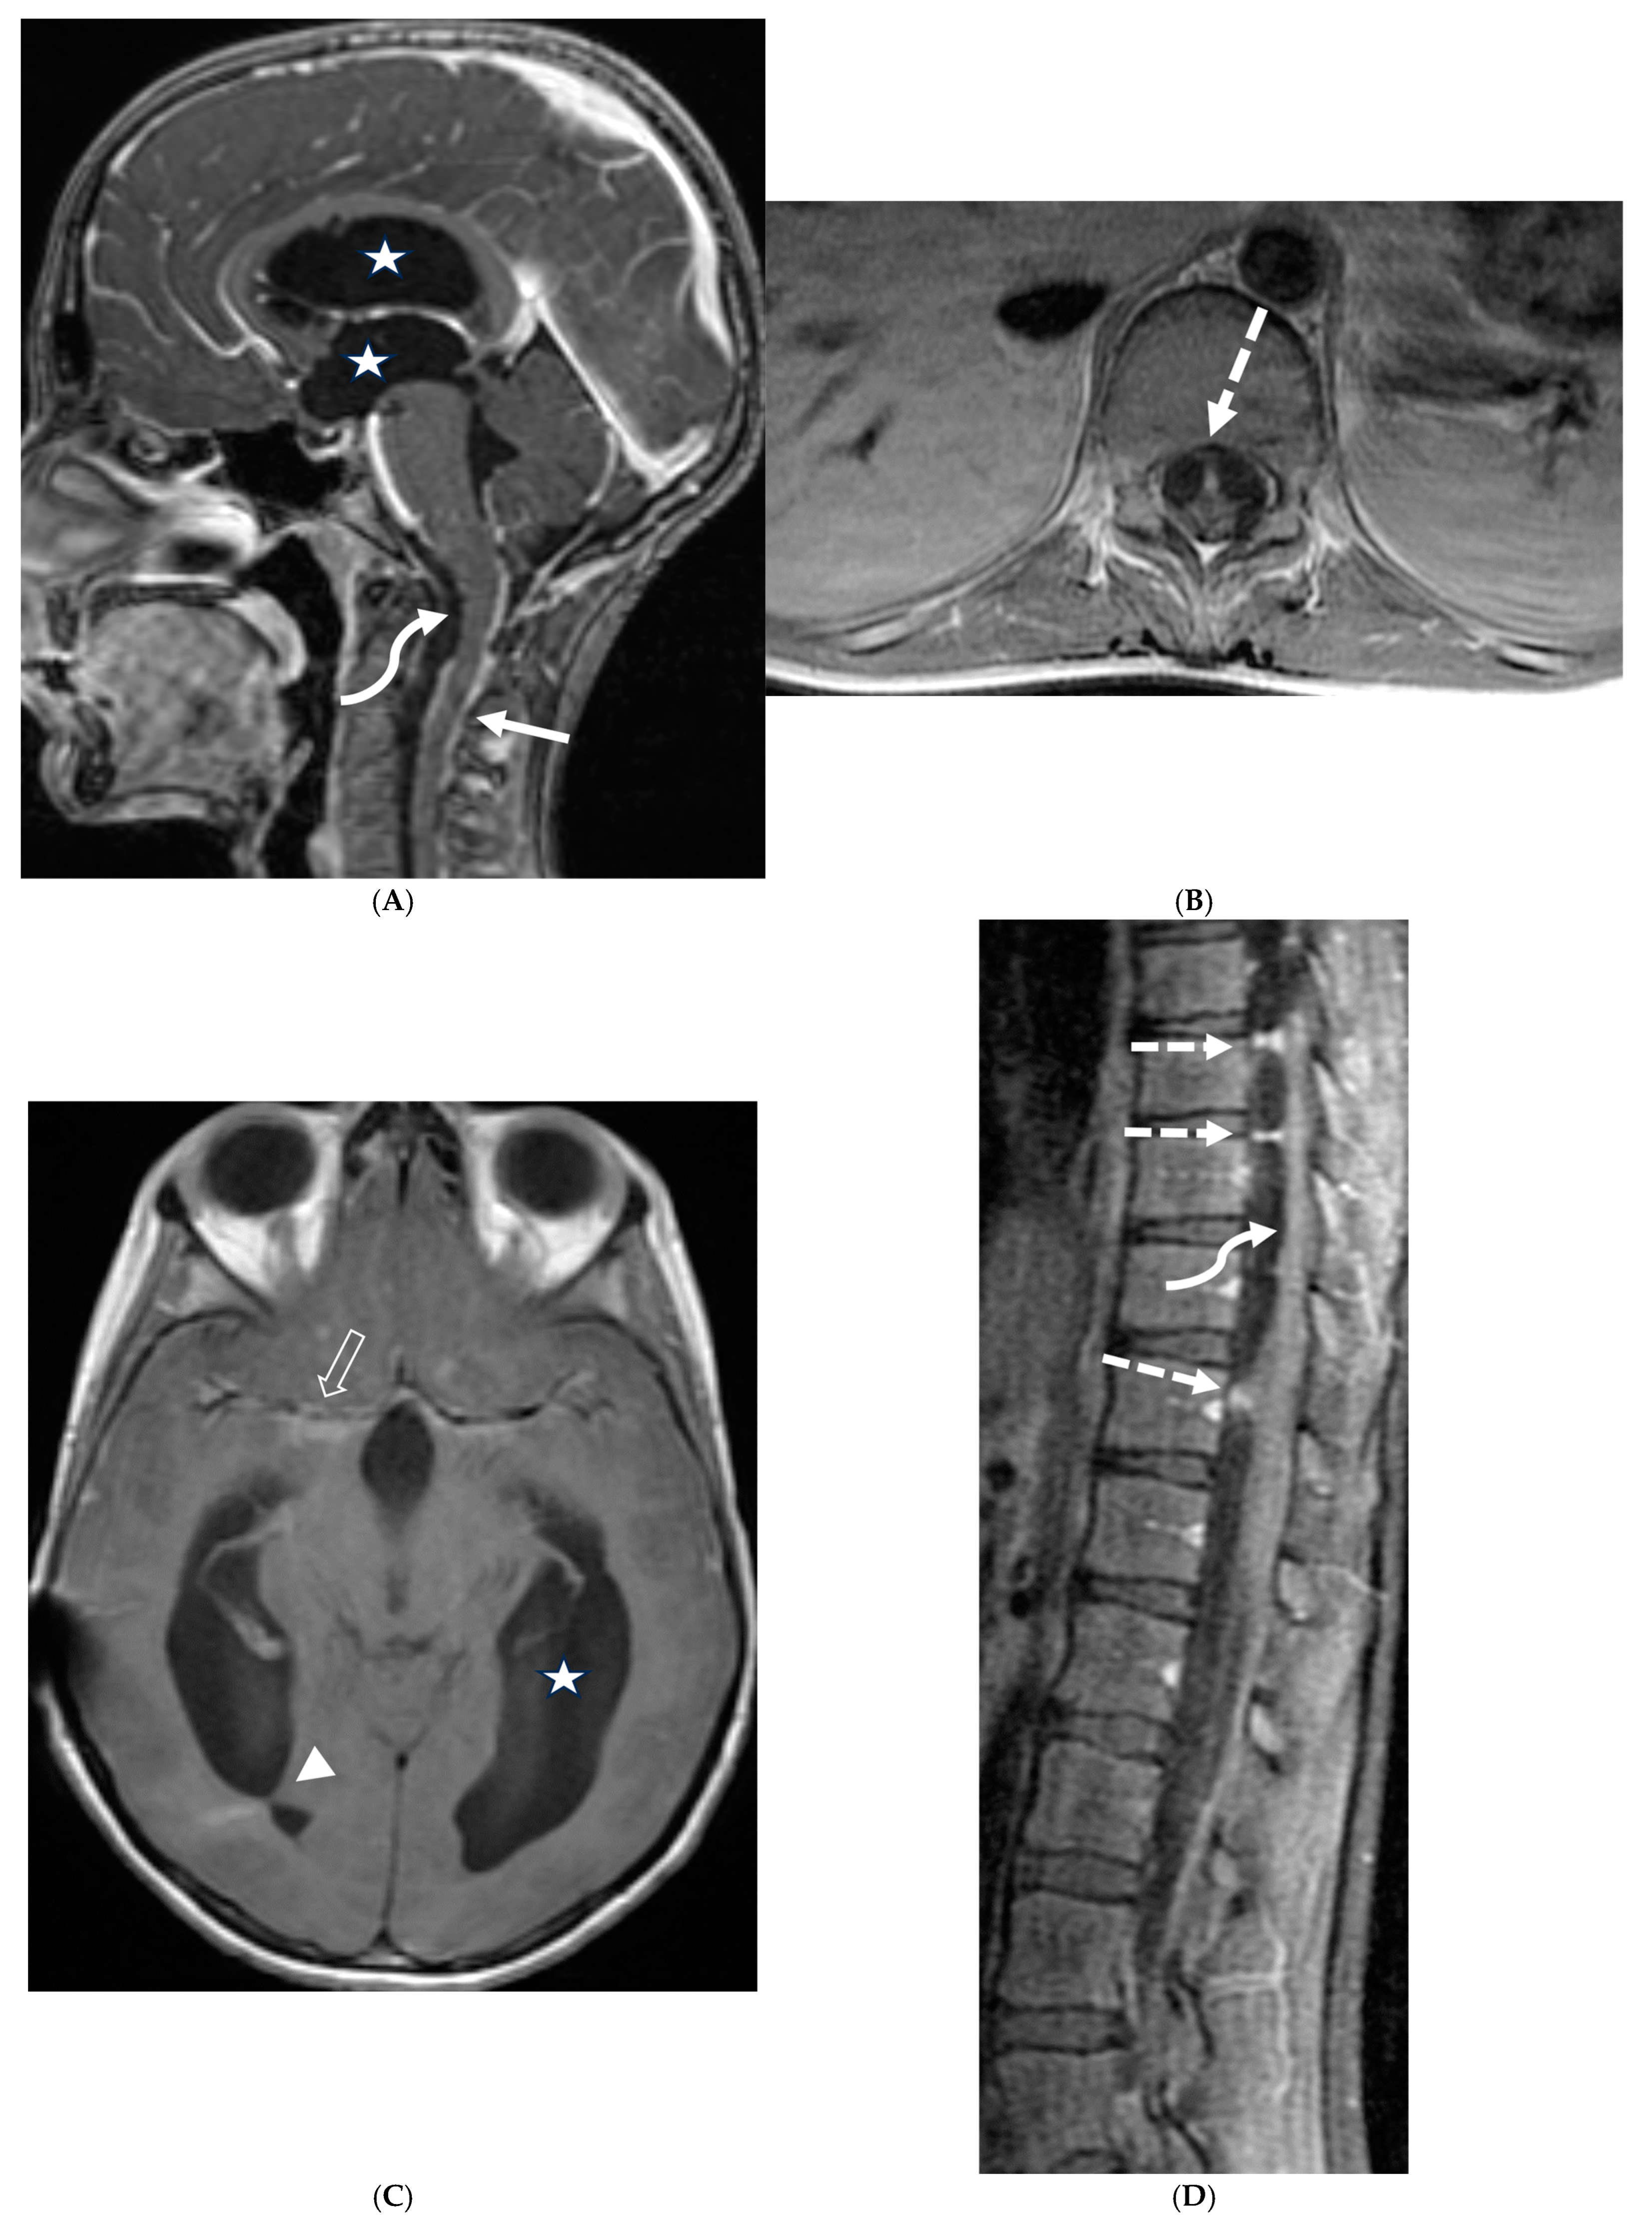

3.2. Neurosarcoidosis

Sarcoidosis is a systemic inflammatory disorder characterized by non-caseating granuloma formation [10,11,12]. Neurosarcoidosis (NS) is uncommon, detected on imaging studies in 15% of the patients, out of which only one-third of them present with clinical symptoms [10,13]. Granulomas, a hallmark of sarcoidosis, can infiltrate cerebral parenchyma, brain vasculature, and cranial nerves [14,15]. Parenchymal involvement leads to motor or sensory deficits, whereas predominant meningeal and subarachnoid involvement leads to cranial nerve deficiencies and vision changes [11]. Contrast-enhanced MRI of the brain and/or the spine is currently considered the standard of care for initial work-up and follow-up in NS [16].

Nodular or diffuse LME, primarily involving the basal meninges, is the most typical finding. It can further spread into the parenchyma via the perivascular spaces [17]. Most cases show focal involvement and are hypointense on T2WI with variable post contrast enhancement [18,19]. Nonenhancing white matter lesions (NEWM), although common, have been shown to have no symptomatic correlation [18]. Optic and facial nerves are frequently involved (Figure 3). The diagnosis of optic neuritis is crucial and regarded as an emergency due to its unfavorable prognosis if not promptly treated [20]. Occasionally [18,21,22], small vessel ischemia related cerebrovascular events occur which manifest clinically with progressive encephalopathy rather than a distinct large vessel stroke [13]. Other rare but important findings include spinal cord and hypophyseal involvement [23]. The mainstay of treatment for CNS sarcoidosis involves corticosteroids to suppress inflammation.

Figure 3.

18-year-old presented with headache, persistent vomiting and weight loss. History of sarcoidosis diagnosed 2 years ago. Axial Fluid Attenuated Inversion Recovery (FLAIR) (A), Axial T1 post contrast (B), Axial T1 inversion recovery post contrast (C) and Coronal Positron Emission Tomograpy (PET) scan (D): There is a heterogeneously enhancing ill-defined area of T2/FLAIR hyperintensity involving the medial aspect of the left globus pallidus (arrows), anterior aspect of the left thalamus and left hypothalamic region. Diffuse enhancement of the basal meninges, tentorium, throughout perisylvian sulci (arrow heads), along the infundibulum, and posteriorly at the craniocervical junction. There is also enhancement along optic nerve sheath (dashed arrows). Features are highly consistent with extensive neurosarcoidosis given the previous history of thoracic sarcoid. PET scan from 2 years earlier demonstrating avid uptake of radiotracer (curved arrows). Radiologically, the differential diagnosis includes tuberculosis and metastatic process. Patient made complete recovery after treatment for sarcoid.